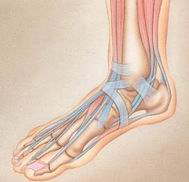

Spezialisten für minimalinvasive Gelenk- und Fußchirurgie

| Hallux valgus Deformitäten | Gelenkerhaltende, anatomisch gerechte Vorfuß-Operationen: -Weichteilpräparationstechnik (Release;Raffung; Sehnen- versetzung) - Osteotomien : Austin; modif. Austin; Reverdin-Green; Scarf; Mau, Z-Osteotomie;(schnellere Heilung) / Basisosteotomie |

| Hammerzehen mit Kontraktur im PIP | OP nach Hohmann; Arthrodese im PIP-Gelenk + Release im Grundgelenk + Stecksehnenverlängerung + Weil-Osteotomie |

| Metatarsalgien II-IV mit plantaren Schwielen | Weichteil-OP im Grundgelenk + dorsale Keilosteotomie /oder Weil-Osteotomie + Sehnentransfer |

| Morton`sche Neuralgie | Entfernung des Neuroms |

| Tarsal-Tunnel-Syndrom | Tarsaltunnelspaltung |